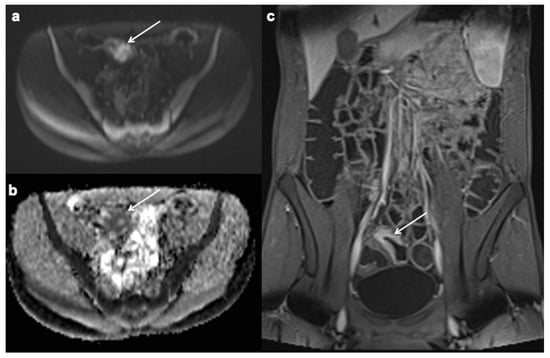

10. Imaging Findings Associated with Active CD Inflammation

11. Imaging Findings Associated with Penetrating CD Inflammation and Complications

| Imaging Findings Associated with Active CD Inflammation |

|---|

Segmental mural hyperenhancement

|

Wall thickening

| Intramural edema |

| Stricture |

| Ulcerations |

| Sacculations |

| Perienteric edema and/or inflammation |

| Engorged vasa recta |

| Fibrofatty proliferation |

| Mesenteric venous thrombosis and/or occlusion |

| Lymphadenopathy |

| Restricted diffusion |

| Diminished motility |